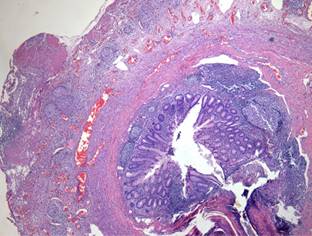

Los resultados de patología de biopsias de apéndice, epiplón y peritoneo reportaron reacción inflamatoria crónica granulomatosa, muy probablemente por tuberculosis (Figura 2), por lo que se confirma el diagnóstico de tuberculosis abdominal.

Figura 2: Apéndice cecal con macrófagos epitelioides y células gigantes tipo Langhans. Ambas demuestran reacción inflamatoria crónica granulomatosa, compatible con tuberculosis.